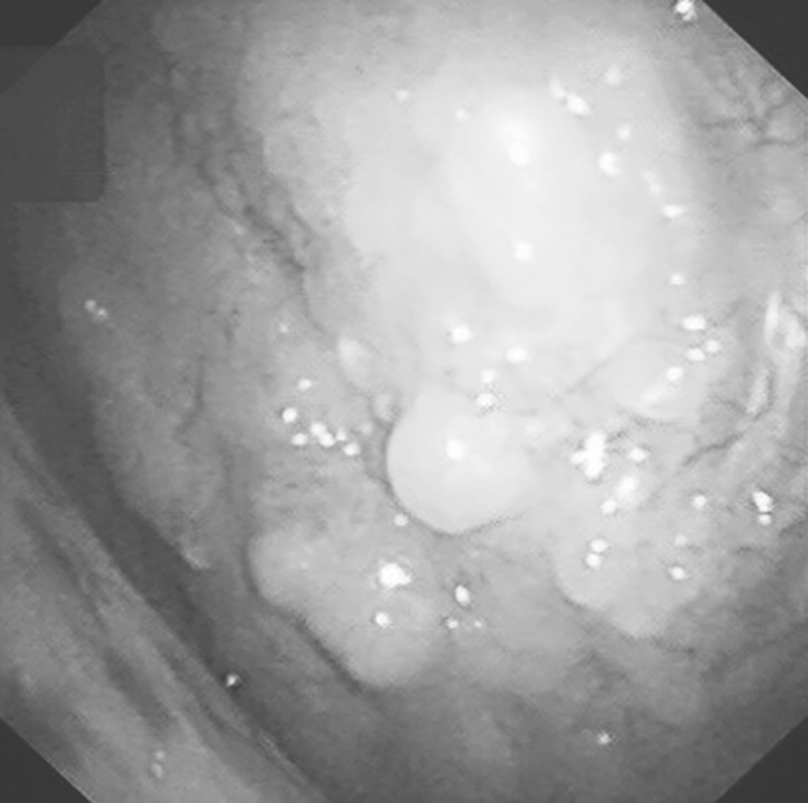

对于上述检查不能确诊者,必要时可经胸腔镜直视下活检。通过胸腔镜检查术(图2-13-5)可以直观、清晰地观察90%~100%的脏、壁胸膜,选择可疑部位钳取组织进行活检,组织标本较大且在直视下获得,因而阳性率大大提高,可达90%以上。

图2-13-5 胸腔镜直视下胸膜活检